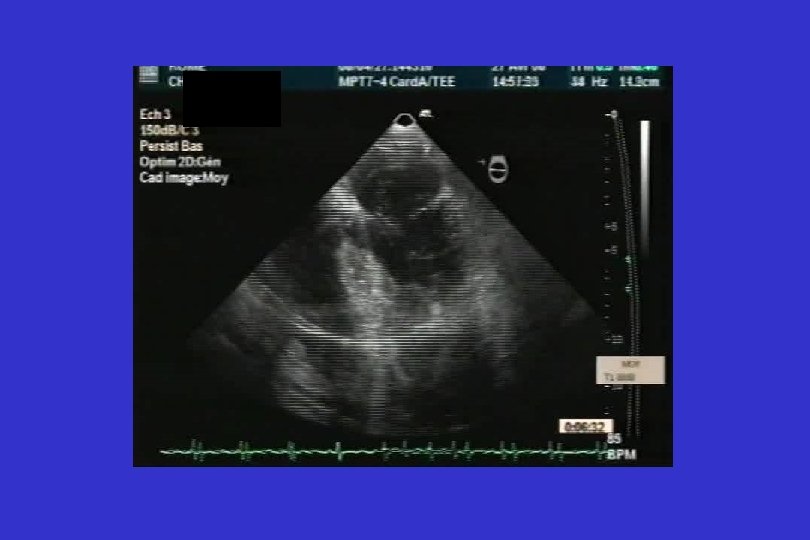

CEC (début 20 h 08) • Pose des canules artérielle fémorale profonde avec reperfusion fémorale superficielle, canule veineuse fémorale par chirurgien en chambre • Contrôle bonne position des canules en ETO • Débit 4 -4, 5 l/min, vitesse de pompe 3600 -4000 tours/min • Décharge VG incomplète mais suffisante • Arrêt des drogues inotropes positives • Maintien PAM > 65 mm. Hg avec Noradrénaline® • Anticoagulation par héparine avec objectif TCA 2 fois le témoin • Maintien protidémie > 50 g/l avec perfusion albumine si besoin

Après 3 h de CEC